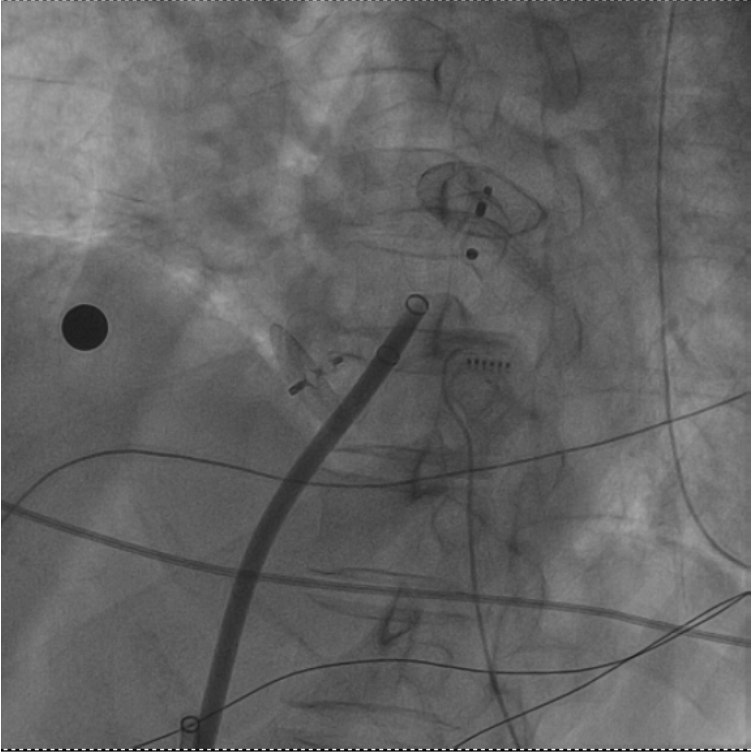

一次穿刺行兩個手術!十堰人醫(yī)成功消除圓孔封堵術后的房顫與血栓

湖北日報客戶端訊(通訊員馬婷婷、劉柳)近日,十堰市人民醫(yī)院心血管內科一病區(qū)成功為一位特殊患者實施了房顫射頻消融加左心耳封堵術。值得一提的是,朱女士此前已接受過卵圓孔未閉封堵術及腦梗塞取栓術,此次手術的成功,不僅彰顯了該…

• 一次穿刺行兩個手術!十堰人醫(yī)成功消除圓孔封堵術后的房顫與血栓

秦楚網(wǎng)-十堰頭條訊?記者 秦洪濤 特約記者 馬婷婷 報道:近日,十堰市人民醫(yī)院心血管內科一病區(qū)成功為一名患者朱女士實施了房顫射頻消融加左心耳封堵術。值得一提的是,朱女士此前已接受過卵圓孔未閉封堵術及腦梗塞取栓術。此次手術的…